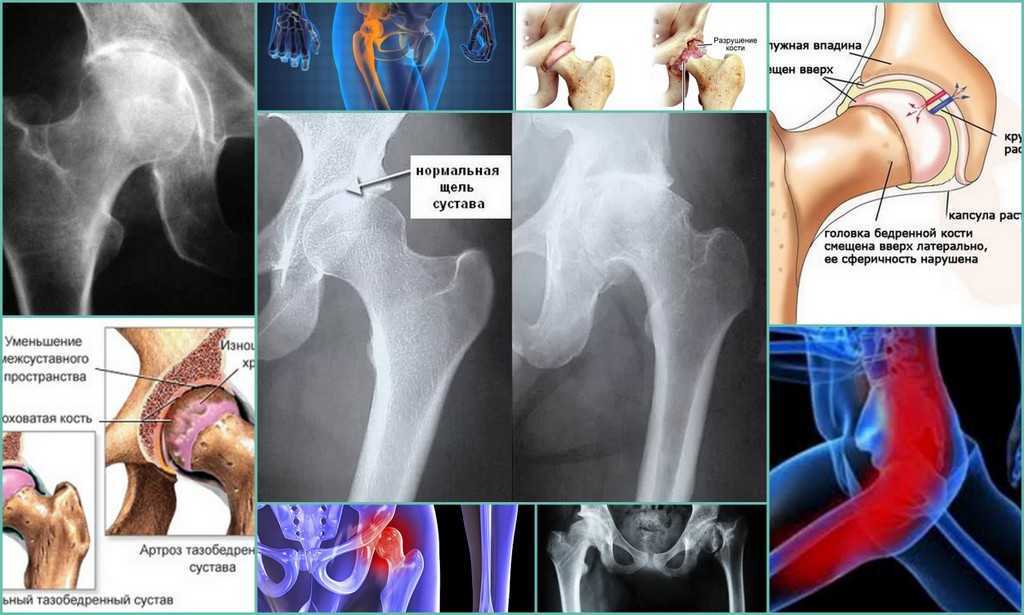

Эффективные методы лечения синовита тазобедренного сустава для быстрого выздоровления

Синовит тазобедренного сустава – это воспаление синовиальной оболочки, которое может привести к болям и ограничению подвижности. Важно своевременно обращаться к специалисту и соблюдать комплексное лечение, включающее как медикаментозную терапию, так и рекомендации по физиотерапии и образу жизни. В этой статье вы найдете полезные советы по облегчению симптомов и ускорению выздоровления.

Синовит тазобедренного сустава

Синовит тазобедренного сустава